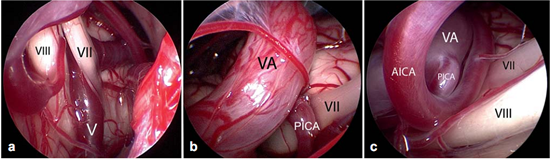

Figure 4内窥镜图像(使用30°内窥镜拍摄)显示了出脑干区的蜗神经和面神经的临近部位,它们被小脑后下动脉(PICA)环所压迫(与figure 2是同一患者)

Figure 5小脑桥脑角区解剖示意图:Ⅴ=三叉神经;Ⅷ=蜗神经;Ⅶ=面神经;Ⅸ=舌咽神经;Ⅹ=迷走神经;Ⅺ=脊附属神经。

Figure 6不同类型的血管压迫。Ⅶ=面神经;Ⅷ=蜗神经

a:由靠近脑干的静脉(Ⅴ)所造成的压迫;

b:椎动脉(VA)和小脑右下动脉(PICA)共同压迫;

c:椎动脉(VA)、下移的小脑右下动脉(PICA)和小脑前下动脉(AICA)共同压迫。